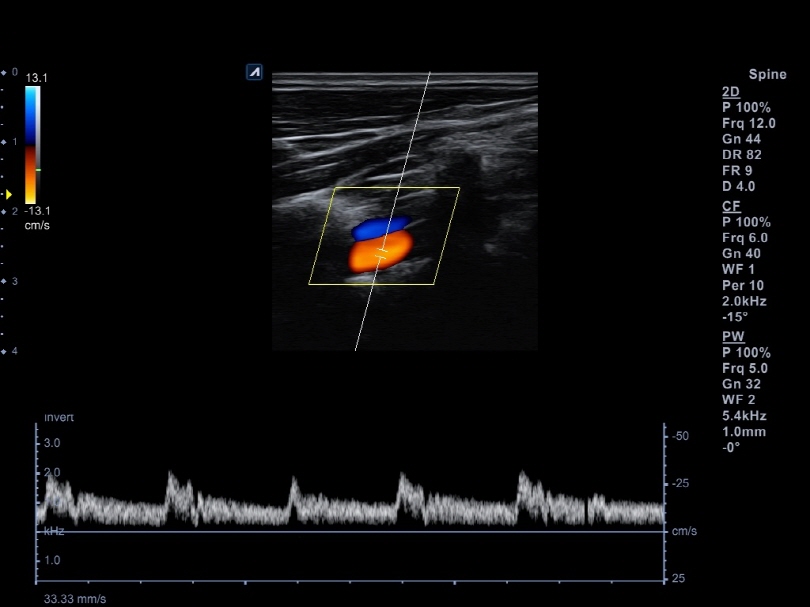

L8-17H

High density linear transducer(8-17MHz)

Application:

Breast, EM, MSK, Vascular, Small Parts

L3-12H

High density linear transducer (3-12MHz)

Application:

Breast, EM, MSK, Vascular, Small Parts

L3-12HWD

High density wide footprint linear transducer (3-12MHz)

Application:

Breast, EM, MSK, Vascular, Small Parts, Appendix

L3-12T

Linear transducer (3-12MHz)

Application:

Breast, EM, MSK, Vascular, Small Parts, Appendix